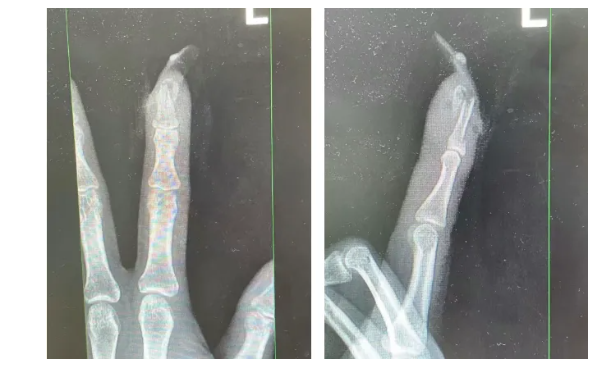

經檢查

王女士指甲斷裂

部分甲床外露

醫生表示如果沒有美甲

傷害不會這么嚴重

萬幸經過手術

王女士恢復良好

王女士受傷手指的X光影像。圖源:杭州市臨平區中西醫結合醫院